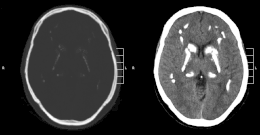

Décrit pour la première fois en 1951[1], le syndrome de Fahr est une maladie se traduisant par des calcifications massives des noyaux gris centraux en l'absence d'anomalie du métabolisme du calcium. Il existe parallèlement des signes neurodégénératifs.

La constatation de calcifications des noyaux gris centraux est fréquent dans de nombreuses maladies. Près de 1 pour cent des scanners du cerveau montrent la présence de calcifications des noyaux gris centraux surtout après 60 ans. Cette constatation ne s'accompagne pas d'une augmentation de pathologie neurologique chez ces individus.